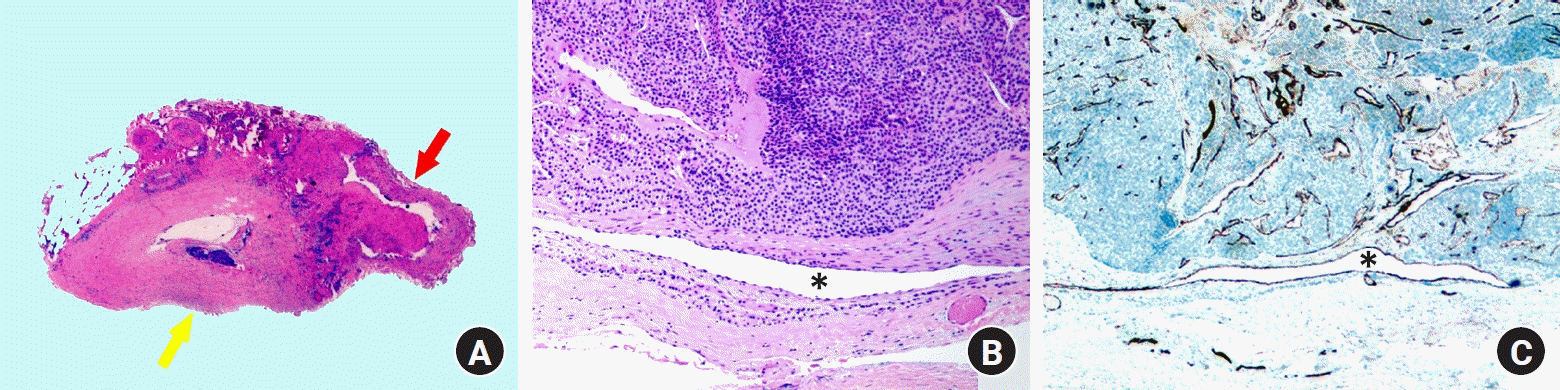

Microscopic examination revealed an encapsulated tumor comprising solid sheets of blue cells, which consisted of round glomus cells with increased vascular spaces (Fig. 3A, 3B). The neoplastic cells were positive for smooth muscle actin immunostaining (Fig. 3C). Sectional views of the tubular structure attached to the tumor revealed the presence of a blood vessel (Fig. 4A, 4B). Notably, a compressed luminal space, positive for the vascular marker CD31, was identified on the tumor’s undersurface (Fig. 4C), indicating a potential connection between the blood vessel of the tumor’s undersurface and the tubular structures (Fig. 1C). These histopathological features suggested that the GT had exerted chronic pressure on the underlying blood vessels, resulting in firm adherence of the vessel to the tumor. Postoperative recovery was uneventful, and the paroxysmal pain resolved immediately following surgery. The patient reported excellent postoperative outcomes at the 3-month follow-up with no observed complications.

The uncommon gross features of the tubular structures connected to both ends of the lesion suggested another possibility: an intravascular GT, an extracutaneous variant that originates from a venous wall and protrudes into the lumen of the affected blood vessel. However, the permanent pathology results ruled out an intravascular GT because the capsule tested negative for CD31 immunostaining, a vascular marker.

Fig. 4.

Histopathological features. (A) A sectional view of the tubular stalk (red arrow) attached to the distal portion of the tumor (yellow arrow), showing the blood vessel (H&E stain, ×15). (B) A luminal space on the undersurface of the tumor, suggesting a compressed blood vessel (asterisk; H&E stain, ×100). (C) A luminal space on the undersurface of the tumor has endothelial cells (asterisk), which are positive for CD31 immunostaining (×200).